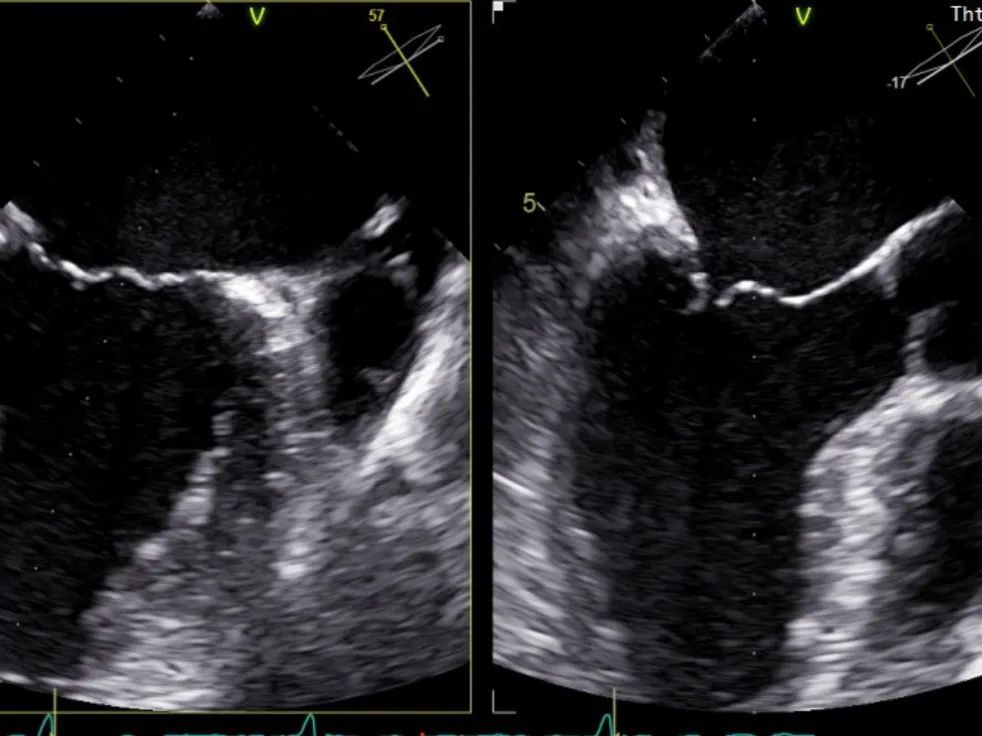

周浩主任继续在食道超声影像引导下进行高难度操作,在第一个二尖瓣夹内侧再置入第二枚二尖瓣夹。

再次反复测试第二枚二尖瓣钳夹的稳定性,超声复查提示二尖瓣反流明显改善,平均跨瓣压差4 mmHg